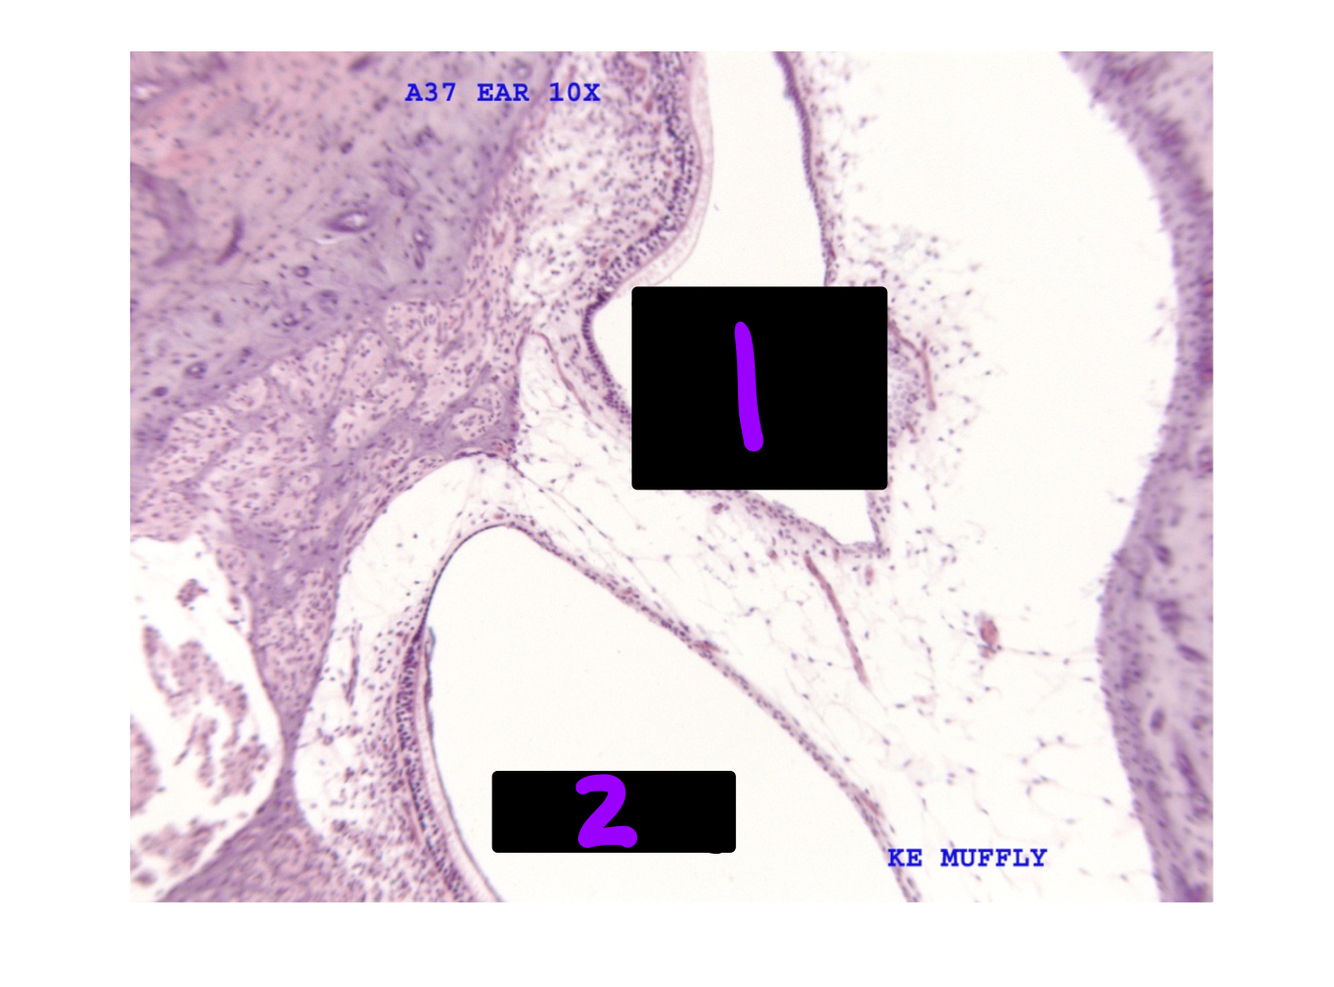

Q

What is #1 and 2?

A

1. Utricle with endolymph

2. Crista ampularis